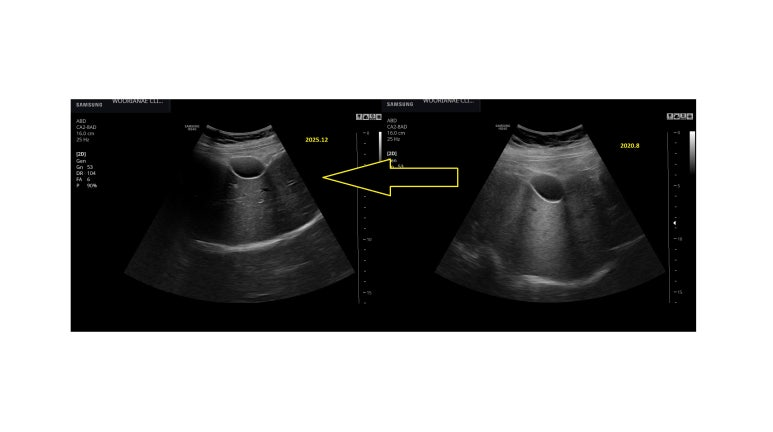

(2021년 이후) 4년만에 복부 초음파 시행

좌측에 결절성 변화

21년에는 매끈한 편이며, 이때 지방간의 정도가 더 뚜렷

담낭 오른쪽으로 결절성 변화, 위축에 의해 공간이 생겨 있다. 그곳에는 장간막이 올라와 있다.

그러나, 과거 사진을 다시 보면 간의 전면부 표면의 윤곽변화는 비슷하다.

단, 지방간 정도가 더 심하여 간의 크기는 뒤쪽으로 더 크다.

지금이라면 진행한 섬유화/간경화 관점의 설명을 하겠지만 과거에는 그럴수 있는 모습으로 넘어간듯하다.

지방간이 줄어들면서 위축과 요철변화가 뚜렷하게 보이는